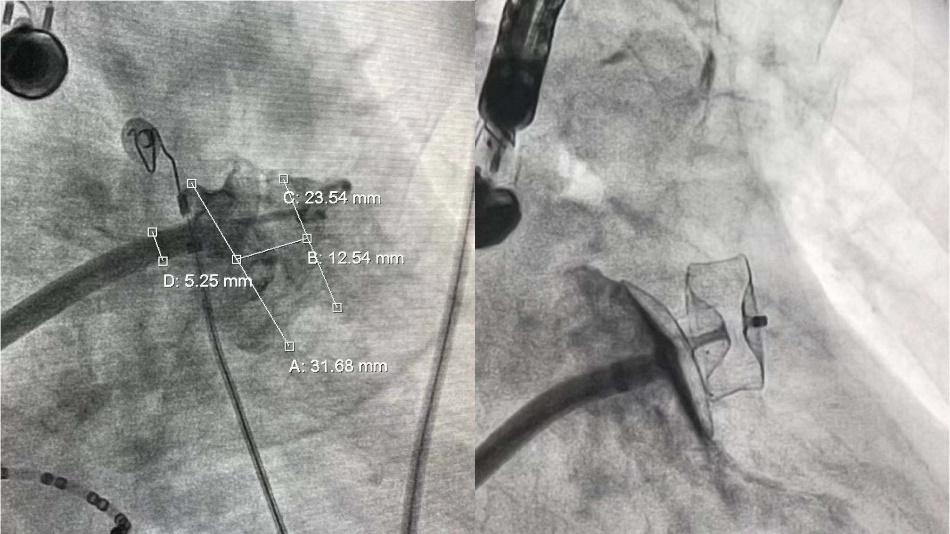

随后行左心耳封堵术,在左心耳 DSA 造影、食道超声测定下,心耳为菜花型,开口约 31 mm,锚定区约 22 mm,选择合适型号(25 mm 固定盘-32 mm 封堵盘)Amulet™左心耳封堵器成功封闭左心耳。

手术非常成功,历时约 3 个小时即完成,封堵过程仅 40 分钟,也显示出 Amulet™预装式封堵器的便利性,患者症状得到缓解,身体康复良好。